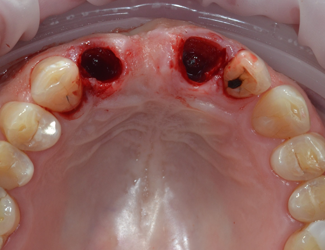

Tidig membranblotta efter 6 veckors läkning.

Avlägsning membran + Mucograft för att återskapa mjukvävnad.